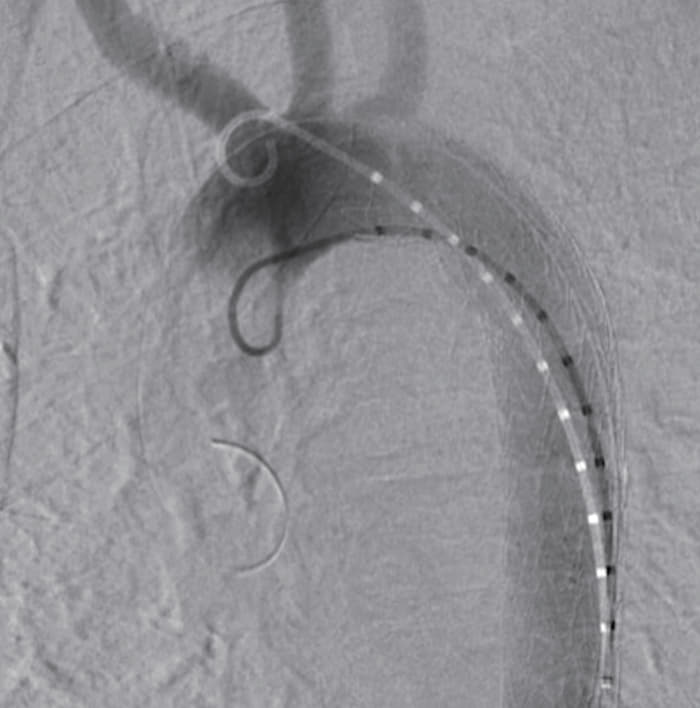

輸血で血圧を維持しつつ全身麻酔にて右鼠径部を切開し総大腿動脈を露出した。ヘパリンを投与したのち8 Frのシースを挿入、ここから注意深くピッグテールカテーテルと血管造影用ガイドワイヤーを上行大動脈まで挿入し、スティッフガイドワイヤーに入れ替えたのち、シースをゴア®ドライシール フレックス イントロデューサシース20 Frに入れ替えた。TAG®コンフォーマブル ステントグラフト アクティブコントロールシステムTGM282815Jを弓部大動脈まで挿入、造影用pigtailカテーテルを上行大動脈まで挿入ののち、LAO45度にてDSAを撮影し、左鎖骨下動脈および大動脈損傷部の位置関係を確認し、マーキングした。ステントグラフトの展開はスティッフガイドワイヤーにて大弯にステントグラフトを押し付けた状態で、中枢端のパーシャルアンカバードステントがわずかに左鎖骨下動脈にかかる程度に固定し展開した。最後にangulation controlを使用し小弯側を十分に圧着させて展開終了とした。DSAにて明らかなエンドリークのないことを確認した。また、展開後は不安定であった血圧も安定した。デリバリーシステムを回収し、右総大腿動脈を修復し、プロタミン投与ののち閉創した。手術時間は58分であり、当院搬入からステント挿入まで約130分であった。

TAG®コンフォーマブル ステントグラフト アクティブコントロールシステムは外傷に対して適応となる唯一のデバイス*であり、構造的に比較的短い中枢ランディングでもシーリング効果を発揮するよう設計されている。更に、本症例ではangulation controlを用いることにより弓部小弯側の大動脈壁にステントグラフトを密着させることができ、エンドリークは生じなかった。外傷性大動脈損傷症例は中枢ランディングが短く、弓部の角度が急峻であることが多いため、小弯側ランディングが問題になるが、アクティブコントロールシステムにより従来以上にエンドリークを抑制するための機能が追加されたことで、外傷性大動脈損傷に対して更に効果を発揮できることとなったと言える。